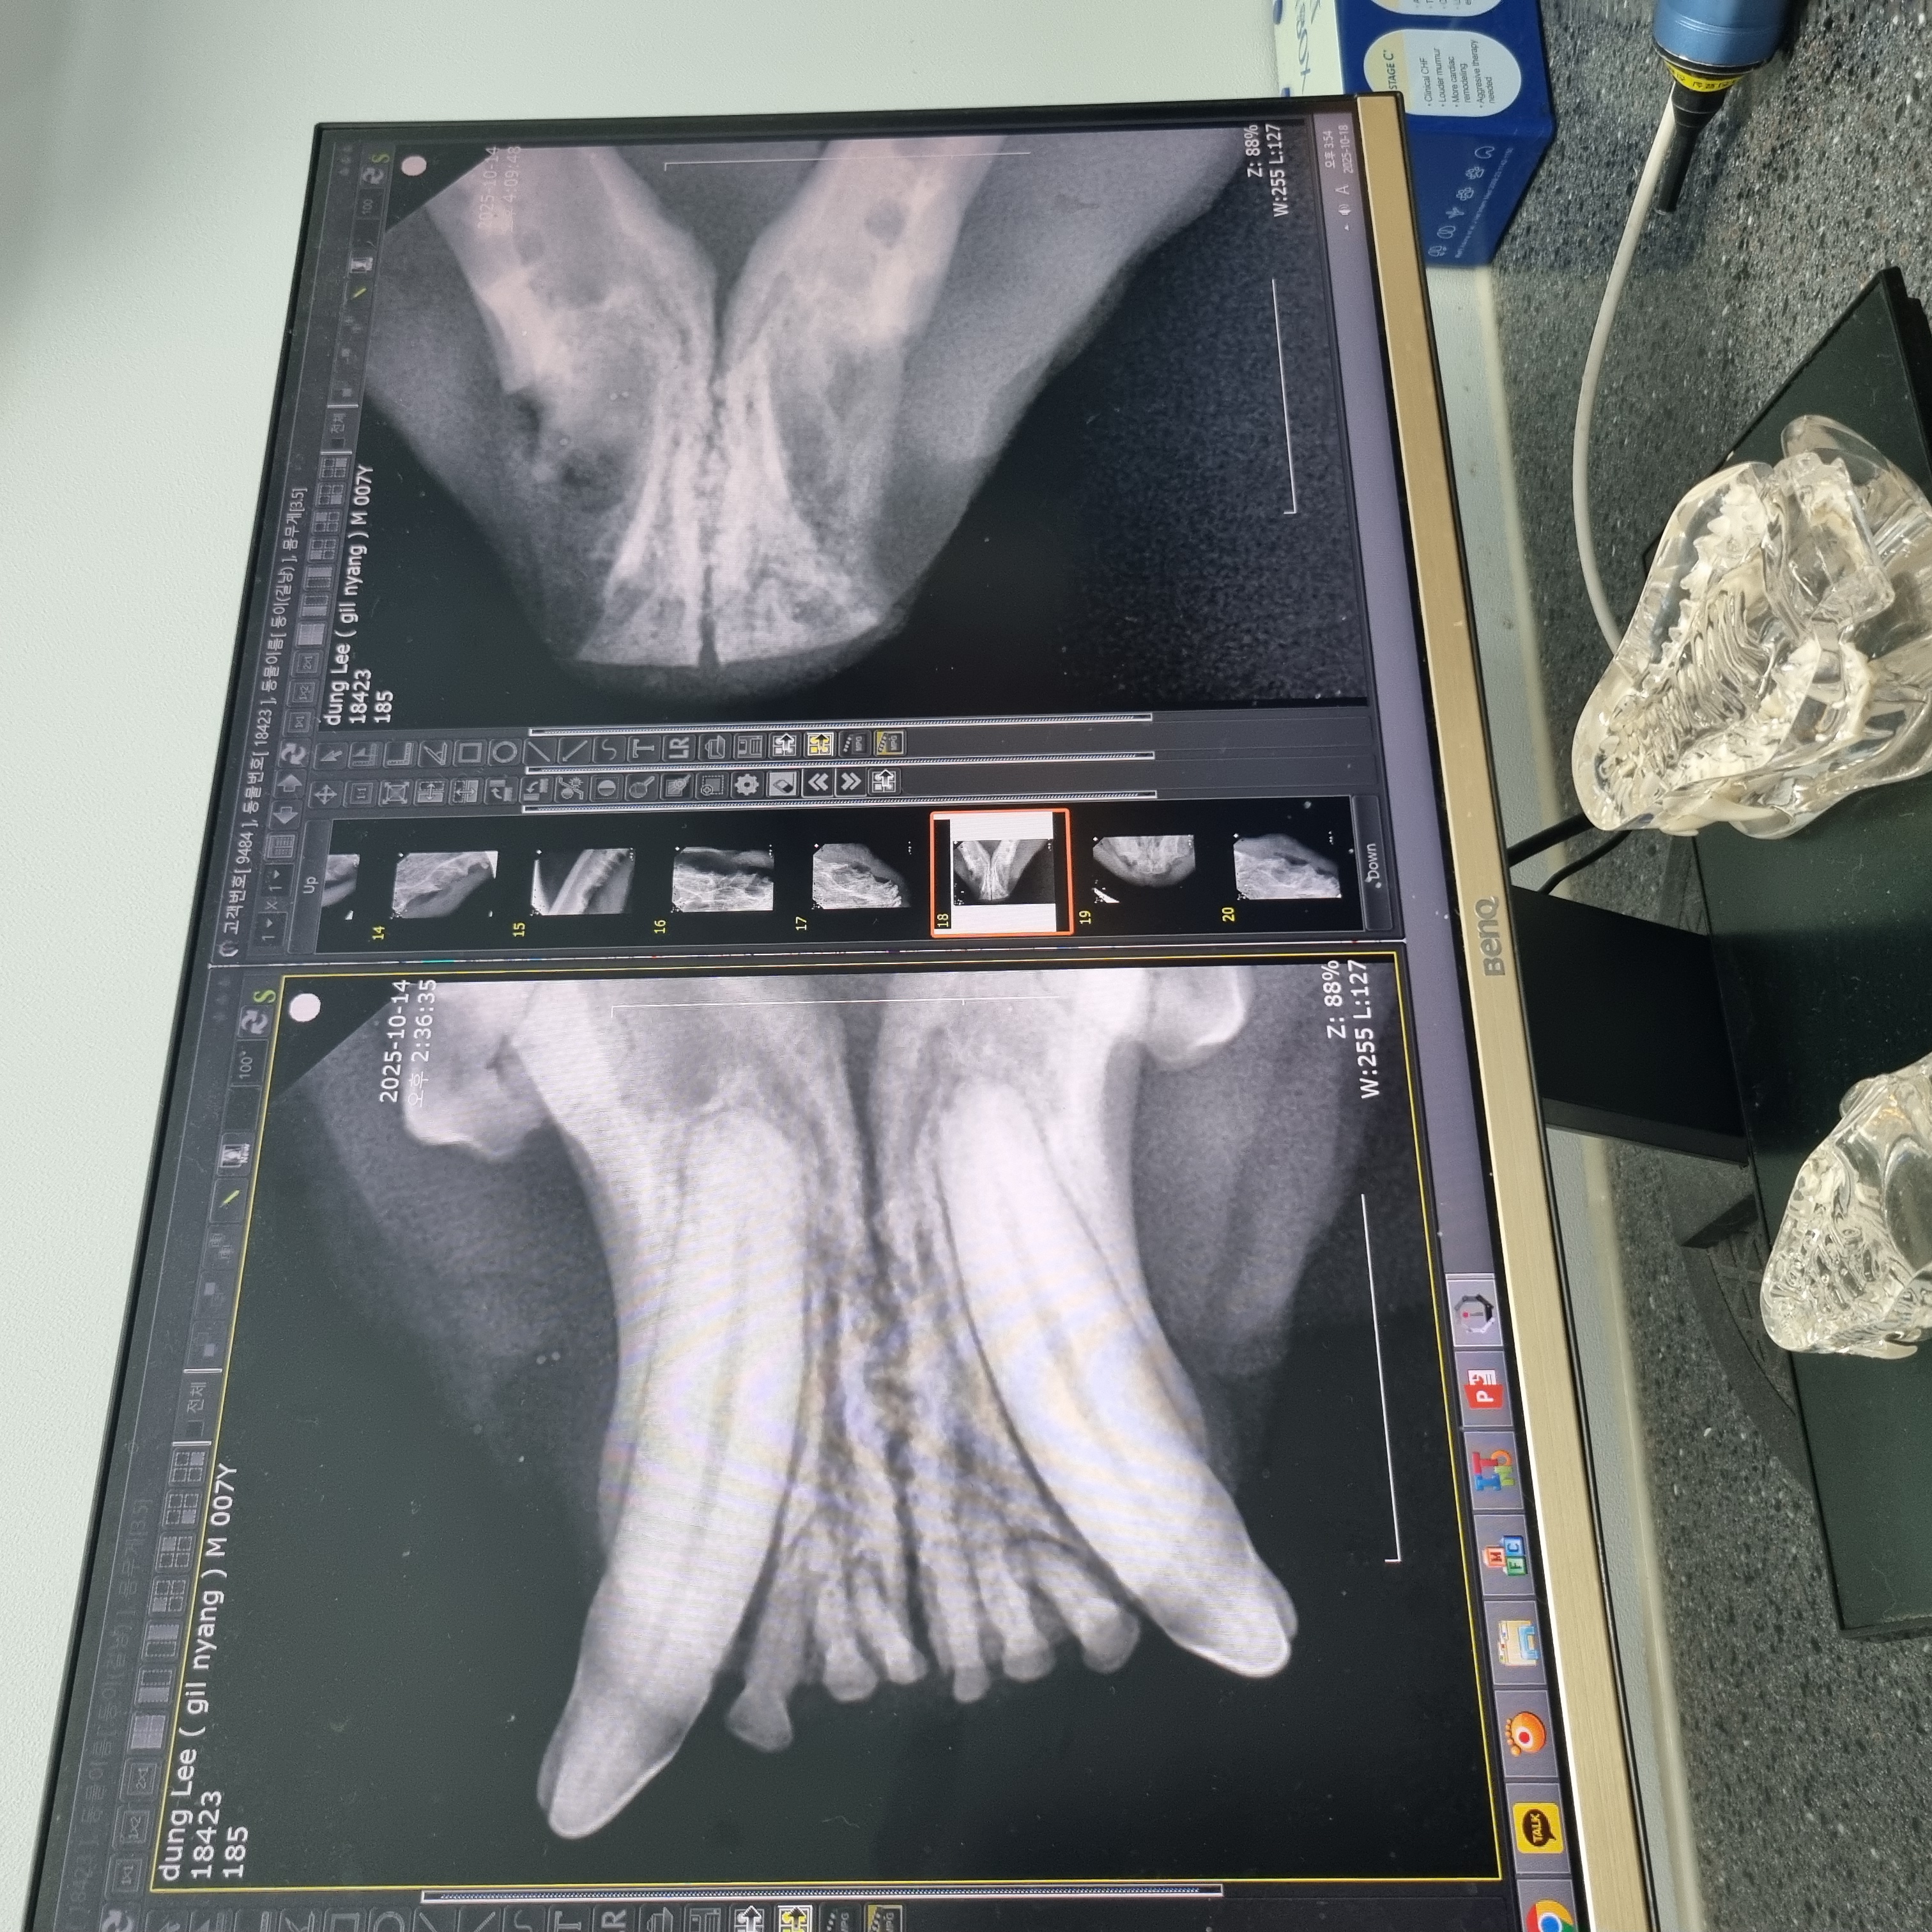

| 치료과정 | 츄르나 파우치를 먹을 때 아주 크게 왕!! 하고 짖는 등 고통을 호소하고 작년보다 최소 2~3킬로는 빠진 모습이라 급히 치료지원신청을 하였고 당일 둥이 구조에도 성공했습니다 둥이는 10월 4일에 구조하게 되었고 이후 병원에 내원하여 정확한 상태를 확인받았습니다. 우리 둥이 마취 후 입 안을 보니 전발치를 해야하는 아주 전형적인 증상이라고 사진을 보여주셨습니다. 둥이의 목구멍 주위에 동그랗고 빨갛게 부은 염증부터 삭아버린 이빨... 얼마나 고통스러웠을지 사진을 보고 마음이 너무 아팠어요. 둥이의 수술을 위해 혈액검사와 키트검사 등을 진행하고 전발치수술을 하게 되었습니다. 수술 이후에는 병원에서 송곳니까지 깨끗하게 전발치한 사진을 치아엑스레이를 찍어 상세하게 보여주셨습니다. 수술을 마친 이후에는 병원에 입원시켜서 수액 처치도 받고 회복에 전념하였습니다. 둥이는 며칠전에 면회때만 해도 좀처럼 기운이 없어 여러 걱정이 많았는데 다행히 어제 면회 때는 기력을 되찾은 모습입니다. 큰 소리로 야옹거리기도 하고 입원실 밖도 돌아다니고 먹고 아주 조금 남은 습식사료까지 싹싹 핥아먹는 모습을 보였습니다. |